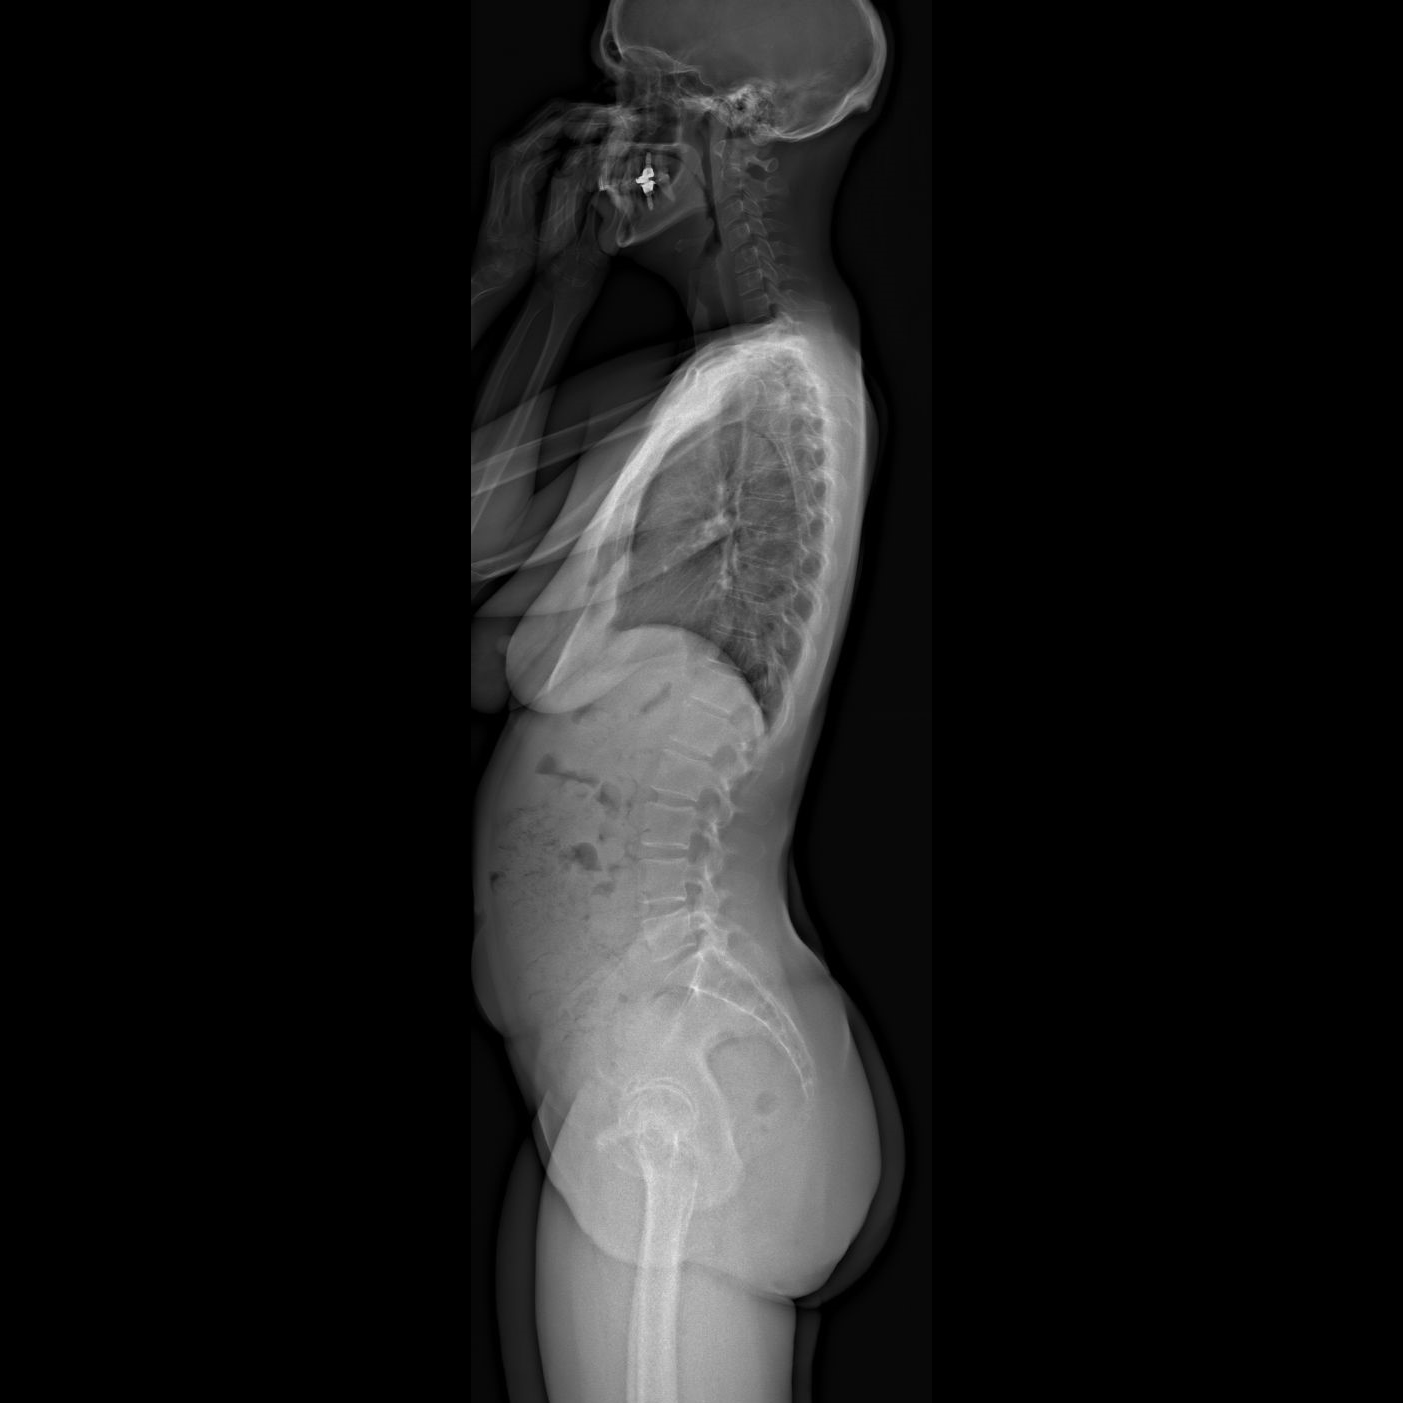

Un examen corps entier, debout, en 2D et en 3D

EOS permet pour la première fois :

• la visualisation du corps entier en position debout ;

• des images de face et de profil ;

• une reconstruction en trois dimensions, utile dans de nombreuses pathologies de la statique du corps.

L’EOS est devenu la méthode de référence pour :

• le diagnostic et le suivi des scolioses et anomalies du rachis ;

• l’analyse de la statique globale du corps, notamment chez les adultes ;

• l’évaluation de la statique pelvienne.